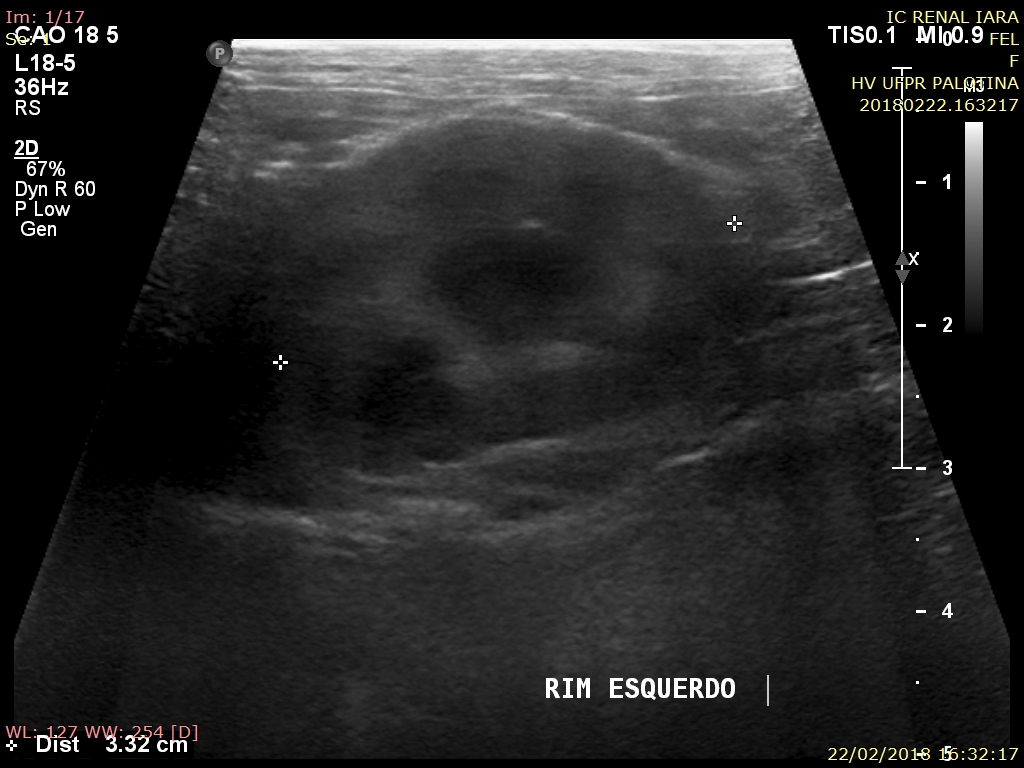

O exame ultrassonográfico é uma ferramenta diagnóstica imprescindível na avaliação da integridade renal, já que fornece informações importantes a respeito da arquitetura e das dimensões renais. Os rins são facilmente visualizados na ultrassonografia, a qual permite avaliar o parênquima do órgão, diagnosticar possíveis afecções, e monitorar o grau de comprometimento tecidual. Os gatos apresentam predisposição ao desenvolvimento de nefropatias, especialmente os mais idosos, por isso o uso do ultrassom demonstra alto grau de importância no diagnóstico precoce. O presente trabalho avaliou 12 gatos provenientes da rotina do Hospital Veterinário da Universidade Federal do Paraná, Setor Palotina, nos quais o tamanho renal demonstrou média e desvio padrão de 3,52 ± 0,45cm para o rim esquerdo e 3,64 ± 0,34cm para rim direito, a ecogenicidade de cortical se mostrou aumentada em sua maioria, sendo um achado normal devido ao acúmulo de gordura tubular. Os parâmetros de topografia, forma, contorno e características de pelve renal se mostraram dentro da faixa de normalidade, sendo as alterações em relação e diferenciação corticomedular, e ecogenicidade de cortical as de maior importância.